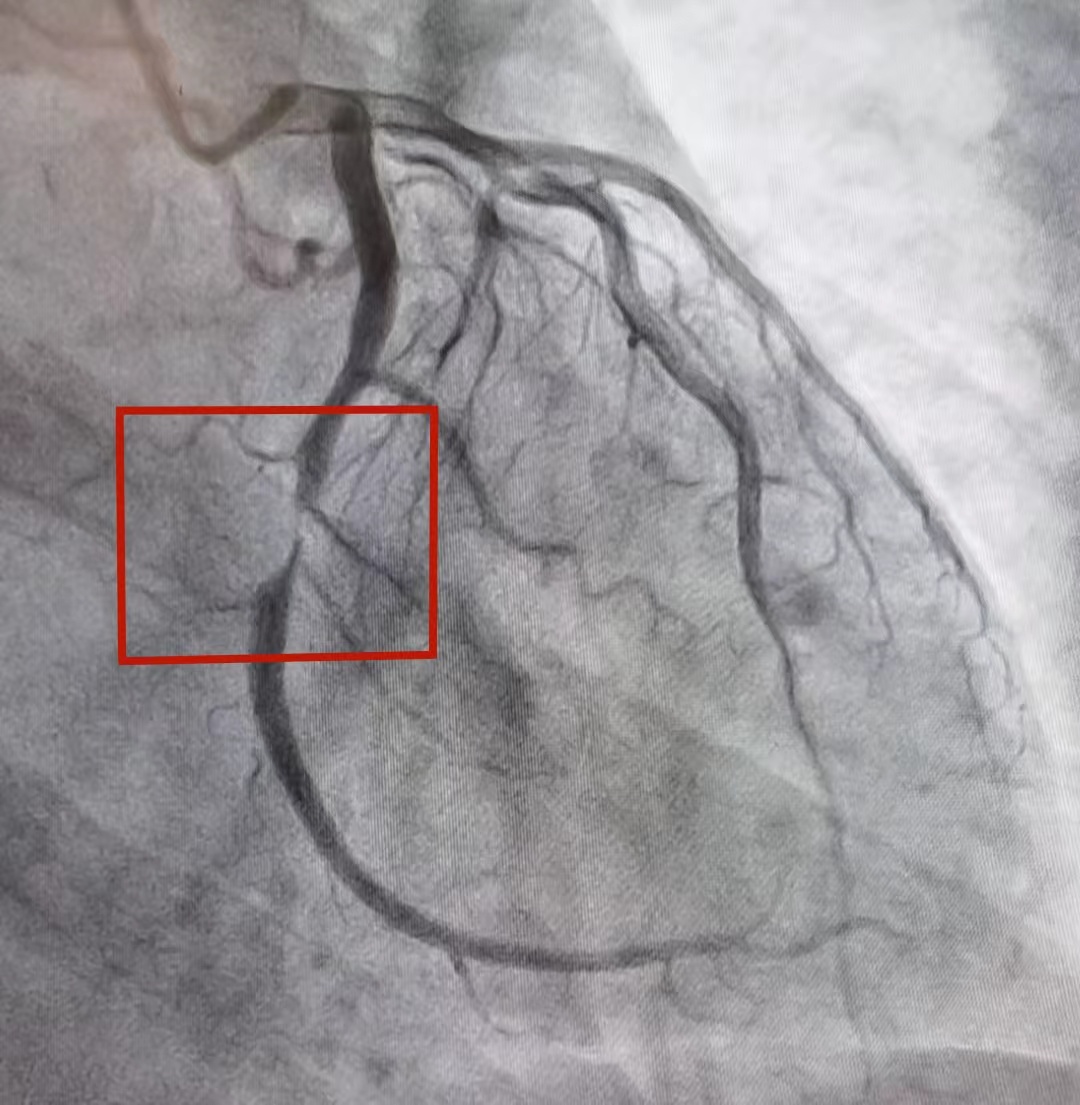

凌晨3点50分,导管室已做好术前准备,周晓斌和徐雷为秦先生行冠状动脉造影术+支架置入术。经多体位冠脉造影检查,发现血管中段次全闭塞,立即于狭窄处植入支架。随着支架植入,血液畅通流动,患者胸痛症状瞬间缓解,全程仅用23分钟便成功开通闭塞血管,这场与死神赛跑的救治任务取得圆满成功。